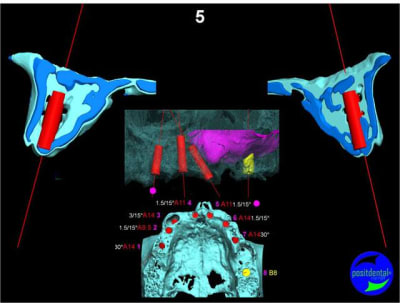

Projet implantaire:

Extraction, pose d’implants Ankylos, pose des piliers Standard définitifs, mise en charge immédiate bi-maxillaire en une chirurgie.

Maxillaire supérieur – extraction 13, 26, 7 implants en MCI, 1 implant en MCR pose summeurs, densification par ostéotme, comblement osseux, bridge provisoire sans fausse gencive avec renfort métallique.

Maxillaire inferieur – extraction 35, 34, 44, 45, 6 implants MCI, comblement osseux, bridge provisoire sans fausse gencive avec renfort métallique.

3D

en attendant la pano voici les coupes de la S.I.A.O.

bien...mais dans certaines zones,surtout postérieures, j'aurais mis plus gros...surtout qu'il y a la place...